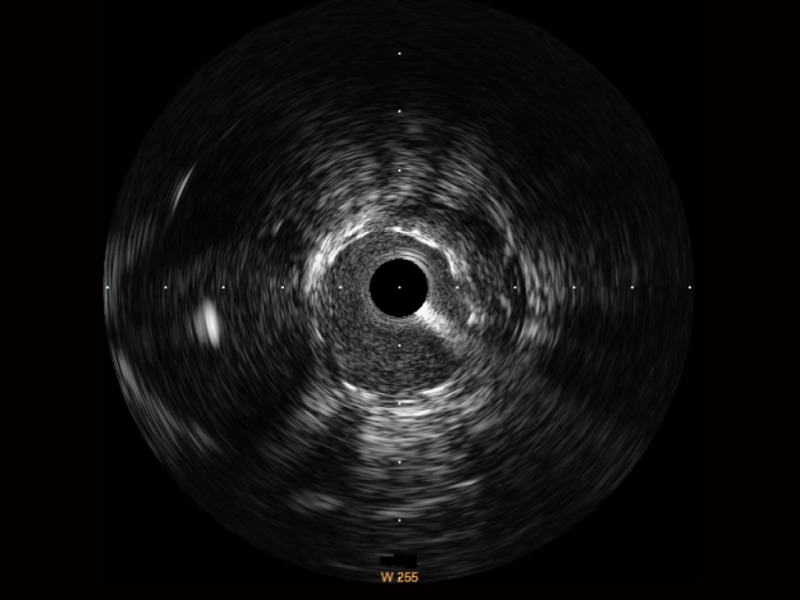

• MILE米乐集团官网宽频IVUS图像

• 传统IVUS图像

对比传统IVUS导管成像,MILE米乐集团官网宽频IVUS图像的近场支架梁显影更细腻,远场中膜外血管仍清晰可辨,兼顾远中近,兼顾分辨力与穿透深度